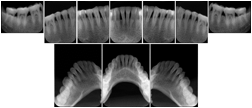

Intra-oral radiography typically involves acquisition of multiple images of various parts of the dentition. Many digital radiographic systems offer customized templates that are used for displaying the images in a study on the screen. These templates may also be referred to as mounts or view sets. The Structured Display Object represents a standard method of encoding and exchanging the layout and intended display of Structured Displays. A structured display object created in this manner could be stored with a study and exchanged with images to allow for complete reproduction of the original exam.

In most standard cases, images are oriented in structured layouts. These structured displays are useful to be shared between providers for reference purposes.

Table OO.1.1-1 shows structured display standard templates, where Viewset ID is based on the Japanese Society for Oral and Maxillofacial Radiology (JSOMR) classification provided by JIRA (Japan Medical Imaging and Radiological Systems Industries Association, www.jira-net.or.jp). Expected or typical teeth to be imaged location, region and designation codes are based on ISO 3950-2010, Dentistry - Designation system for teeth and areas of the oral cavity. For all the hanging protocols listed in OO.1.1-1, the value to use for Hanging Protocol Creator (0072,0008) is "JSOMR" and the value to use for Hanging Protocol Name (0072,0002) does not include "JSOMR" (e.g., "DL-S001A", not "JSOMR DL-S001A").